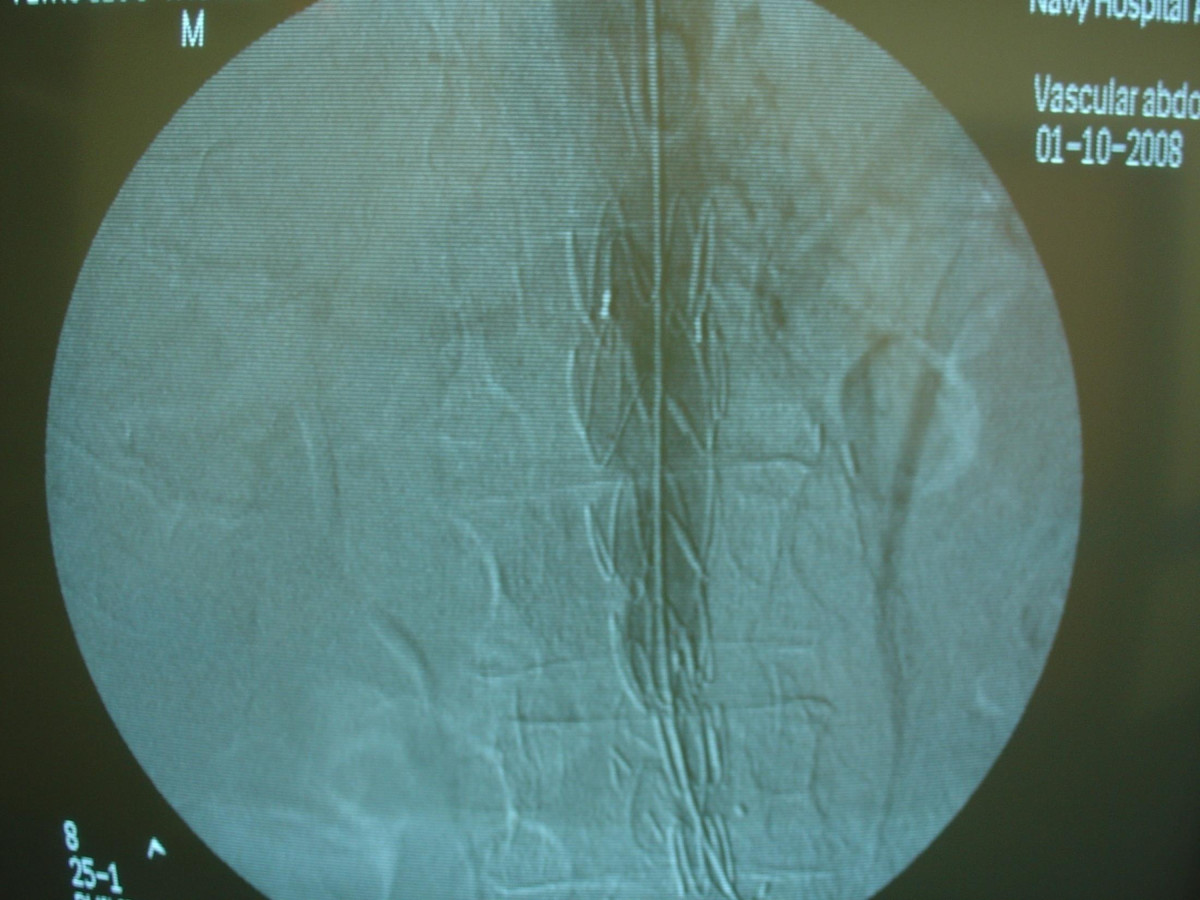

Endovascular repair of anastomotic abdominal aortic aneurysm, after aortobifemoral bypass

Vascular Clinic, Naval and Veterans Hospital of Athens

AVEM2009-Thessaloniki